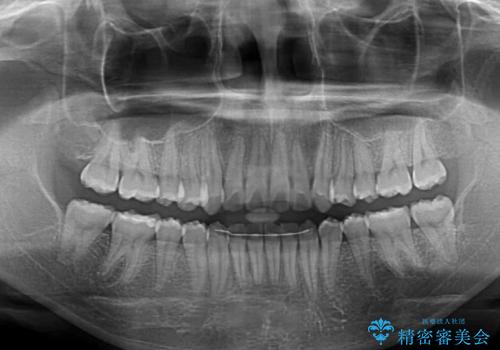

インビザラインでの治療を希望されていましたが、前歯のクロスバイトや下顎小臼歯の捻転が認められたため、インビザライン単独で治療を行うよりも、ワイヤー装置を併用した方が、治療期間の短縮やトラブル回避できると判断し、ワイヤー装置を併用することとしました。

まずはワイヤー装置により前歯のクロスバイトと下顎小臼歯の捻転を改善し、その後インビザラインにより全体を整える矯正治療を行うこととしました。

前歯のクロスバイトは、インビザラインでの改善中に前歯に過剰な力がかかり、歯髄壊死や歯肉退縮を引き起こすことがあります。また下顎小臼歯は寸胴型のため、捻転を排除することが難しいことが知られています。

それをワイヤー装置にて速やかに改善することで、トータルでの治療期間を短くすることができます。